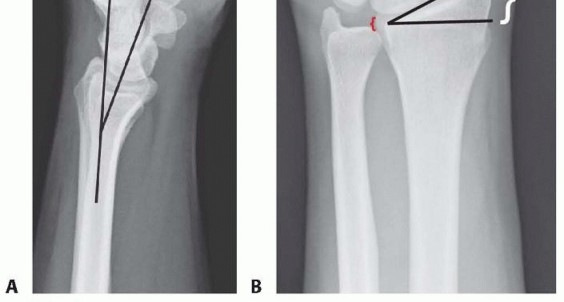

Distal radius fractures occur at the distal end of the bone, originating in the metaphyseal region and often extending to the radiocarpal and distal radioulnar joints (DRUJ).Distal radius fractures can be classified as stable or unstable and extra- or intra-articular to assist in treatment decisions.Fractures may angulate dorsally or volarly and may have significant comminution depending on the energy of the injury and the quality of the bone.Percutaneous pins or K-wires, typically 0.062 or 0.045 inches, can be used for treatment of simple intra-articular or extra-articular fractures with mild comminution and no osteoporosis.Percutaneous pins can aid reduction and stabilize the fragments in a minimally invasive manner.Percutaneous pins can support the subchondral area of the distal radius and maintain the articular reduction in highly comminuted fractures, which is useful when combined with other fixation methods.Smooth percutaneous pins may also be placed across the physis to maintain a reduction in children with minimal risk of a growth arrest.Highly comminuted fractures are more difficult to fix rigidly and often require external and/or internal fixation to maintain alignment during healing.External fixators can be hinged or static and may or may not bridge the wrist joint.K-wire fixation of extra-articular and simple intra-articular fractures has received more support over the last few years after several prospective randomized trials comparing K-wire fixation to volar plating has shown no difference in outcome at 1 year. FIG 1 • Anatomy surrounding the radial sensory nerve branch in the forearm.

Distal radius fractures needing no reduction and those that are stable after reduction typically recover functional range of motion with minimal long-term sequelae.Three parameters that affect outcome include articular congruity, angulation, and shortening. 21,26Two millimeters or more of articular surface incongruity of the distal radius can lead to degenerative changes, pain and stiffness.Dorsal angulation can lead to decreased range of motion and increased load transfer to the ulna. Radial shortening can lead to decreased range of motion, pain, and ulnar impaction of the carpus.